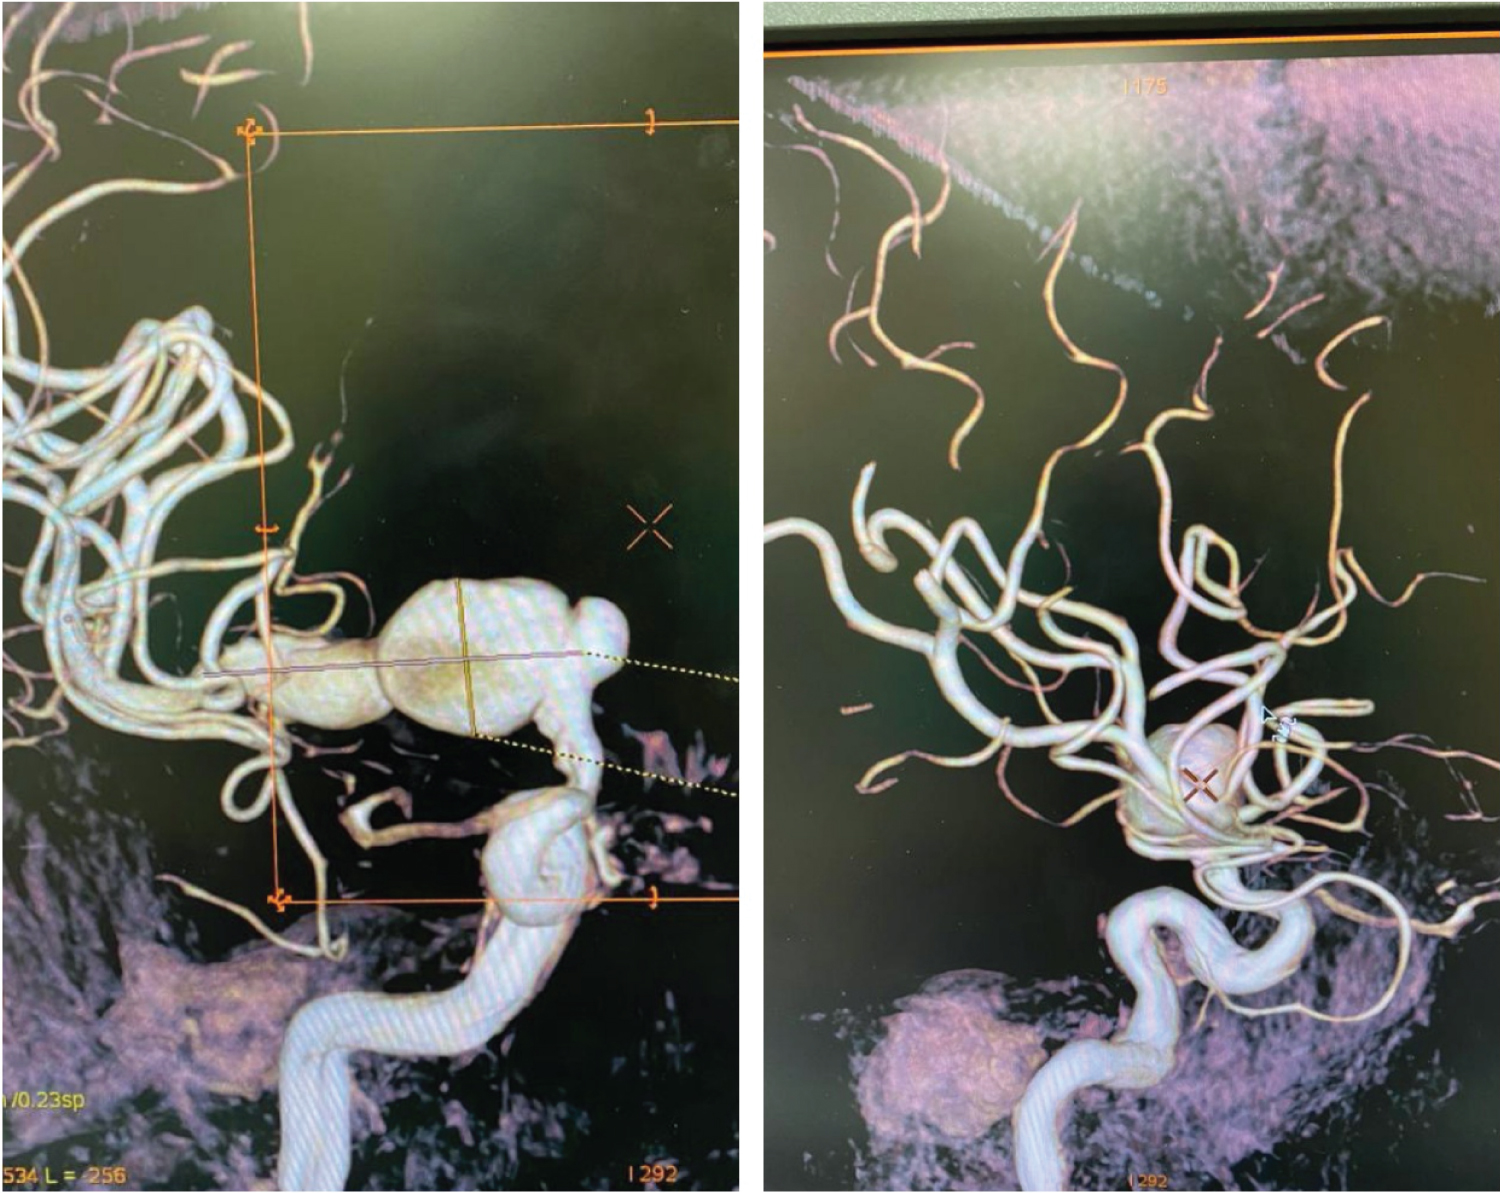

He remained neurologically stable, and at two weeks post-intervention had improvement in the left upper limb power grade from 4/5 to 4+/5. At three months post-endovascular intervention, his power is now 5/5 in all limbs, and 3-month angiogram (Figure 2) shows no aneurysmal recurrence (OKM grade D). He remains on dual anti-platelet therapy, which will be continued for a minimum of one year.

Figure 2: Post-flow diverter placement, showing complete exclusion of aneurysmal segment from circulation in AP (left) and oblique (right) views. Graded as OKM D. View Figure 2